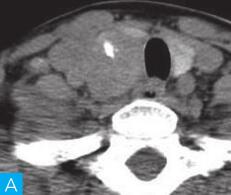

甲状腺CT检查:CT检查设备为256层iCT,病人采取仰卧位,扫描范围自外耳道平面至下颌角以下,常规扫描层厚为0.9mm、层间隔0.9mm,电压120kV,管电流280mA,矩阵512×512;经右肘静脉团注法增强扫描,碘海醇80ml,流速4ml/s,动脉期25秒扫描,静脉期60秒扫描。见图1。

图1 甲状腺CT

A、B.甲状腺CT横断面平扫;C~H.甲状腺CT横断面增强

答案A 解析:甲状腺左叶病变边界清楚,形态较规则,密度不均匀,部分为实性改变,部分为囊性灶,其内可见斑点状粗大钙化灶,气管及食管向右推移,左侧颈总动脉向左后推移,胸锁乳突肌向左前推移。根据表现病变不是单纯囊性病变。

CT平扫可见甲状腺左叶圆形以低密度为主病灶,大小为8.0cm×6.5cm,边界清晰,边缘尚光整,其内密度不均匀,低密度区CT值18HU,部分密度稍高,并可见斑点状粗大钙化影;CT增强后,甲状腺左叶病变呈不均匀渐进性强化,结节状改变,动脉期强化区CT值99HU,静脉期CT值85HU,且强化范围增大,提示该病变的血供较为丰富,应该考虑肿瘤样病变,结节性甲状腺肿可能性大。

本病例CT扫描发现起源于甲状腺较为容易,但要观察病变是囊性、实质性或囊实性及其供血,CT增强扫描十分必要,易于显示囊实性病变及其供血情况,其结节状改变更加显著,有助于判定病灶的血液供应情况。本病例基本征象为类圆形、边缘清晰、内粗大钙化、结节状强化之肿块。